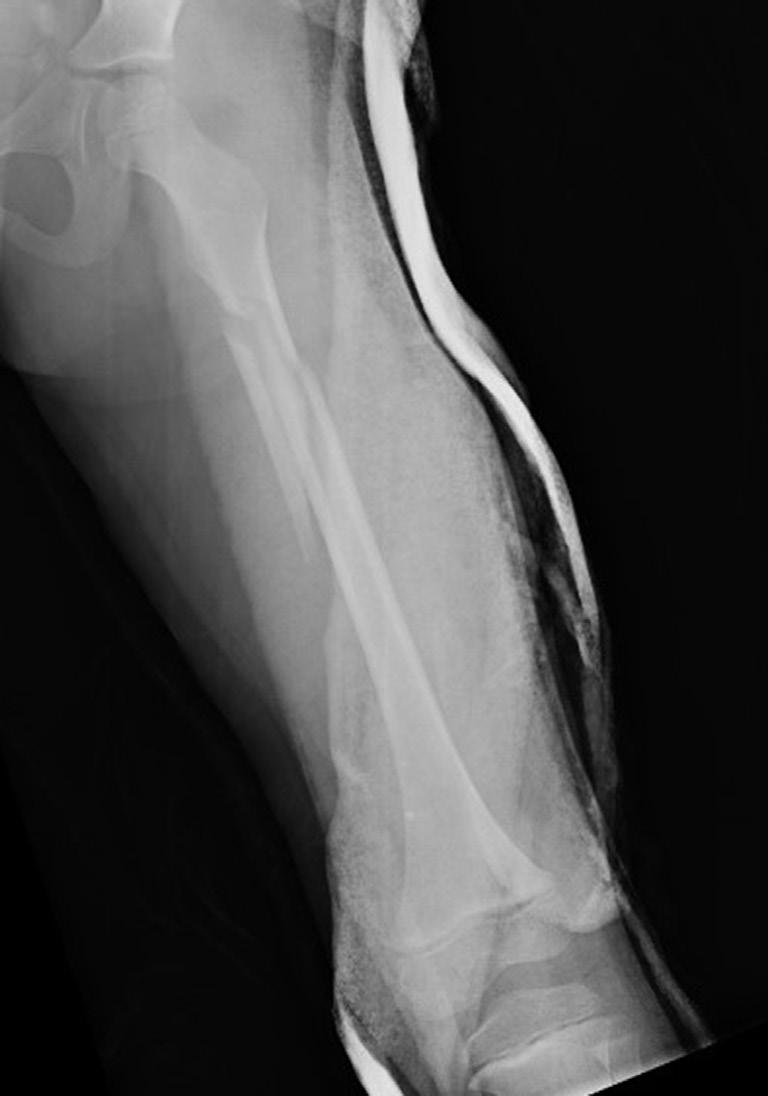

Children also vary from adults as bone overgrowth has been seen in pediatric fracture healing. Fractures distant from the physis can also result in changes in growth patterns. This is particularly evident in overgrowth after femoral shaft

fractures; some investigators have hypothesized that disruption of the periosteal sleeve or increasing vascularity of the bone after a fracture increases longitudinal growth.19,23 This phenomenon most frequently compensates for fractures that heal with shortening but occasionally results in the injured limb being longer. The same cells and processes that govern normal growth are involved in fracture healing.55 Studying growth mechanisms with microarray technology demonstrates the complexity of the genetic response to a fracture. In a study of femoral overgrowth mechanisms in a rat model, more than 5000 genes in the proximal femoral physis were noted to respond significantly to fractures. Genes related to vascular development and growth were downregulated, which casts doubt on the widely held assertion that femoral overgrowth is a consequence of increased vascularity in the limb after a fracture.35 It has been postulated that mechanical factors, such as tension within the surrounding periosteum, may have some control over the growth rate.18,19 This is clinically best exemplified by posttraumatic tibia valgus after proximal tibial metaphyseal fractures in children (the Cozen phenomenon).56–58 Recent basic science data by Halanski et al59 confirmed that disruption of the periosteum would accelerate growth. This pattern of overgrowth is not observed in adult fracture healing, and thus, fracture shortening at union will be permanent.

GROWTH ARREST LINES OR GROWTH SLOWDOWN LINES

In radiographs of bones that were fractured several weeks to months previously, transverse lines may be seen in the metaphyseal region. These lines are usually referred to as Harris growth arrest lines, or the transverse lines of Park,60 and are unique to children’s bones after a fracture or injury. These transversely oriented trabeculae occur in bones that are normally growing rapidly (e.g., femur or tibia) and in those in which the trabeculae are predominantly longitudinally oriented (Fig. 1.3). When growth deceleration occurs, as happens immediately after a fracture of an extremity, the bone is, in effect, standing still and making transversely oriented trabeculae. The calcified cartilage and bone formed has increased density and is evident radiographically after further growth. Arrest lines should parallel the physeal contour if the physis is growing normally. After a fracture, these lines are typically visible 6 to 12 weeks after injury and can provide the orthopedist with the ability to assess and predict abnormal growth.60 A specific effort should be made to look for these arrest lines during radiographic evaluation of childhood fractures, especially those involving the physes, because lines that do not parallel the physis indicate an area of physeal damage or an osseous bridge.60,61 Arrest lines that do not parallel the physis point to an area of abnormal physeal growth.

The physes that grow more rapidly (e.g., the distal end of the femur or the proximal end of the tibia) have arrest lines farthest from the physis. In the metaphyseal areas of bones, where the slowest growth occurs, transverse trabeculae may be difficult to see radiographically or may not form at all.

Transversely oriented Harris lines may also result from any type of stress on the bone that causes a temporary slowdown in the formation of longitudinally oriented bone. Such stresses include systemic illness, fever, and starvation,

Fig. 1.3 Anteroposterior (A) and lateral (B) radiographs of the knee of a 12-year-old child 6 months after a femoral shaft fracture. Arrest lines parallel to the physis can be seen in the metaphyseal area of the distal end of the femur and proximal tibia (arrows). The temporary depression of growth at the time of injury results in more horizontal trabeculae being laid down, thereby increasing the density of bone at that level.

as well as skeletal trauma.62 Similar lines can be seen in skeletally immature patients being treated with bisphosphonates, and are called zebra lines in osteogenesis imperfecta patients.63,64